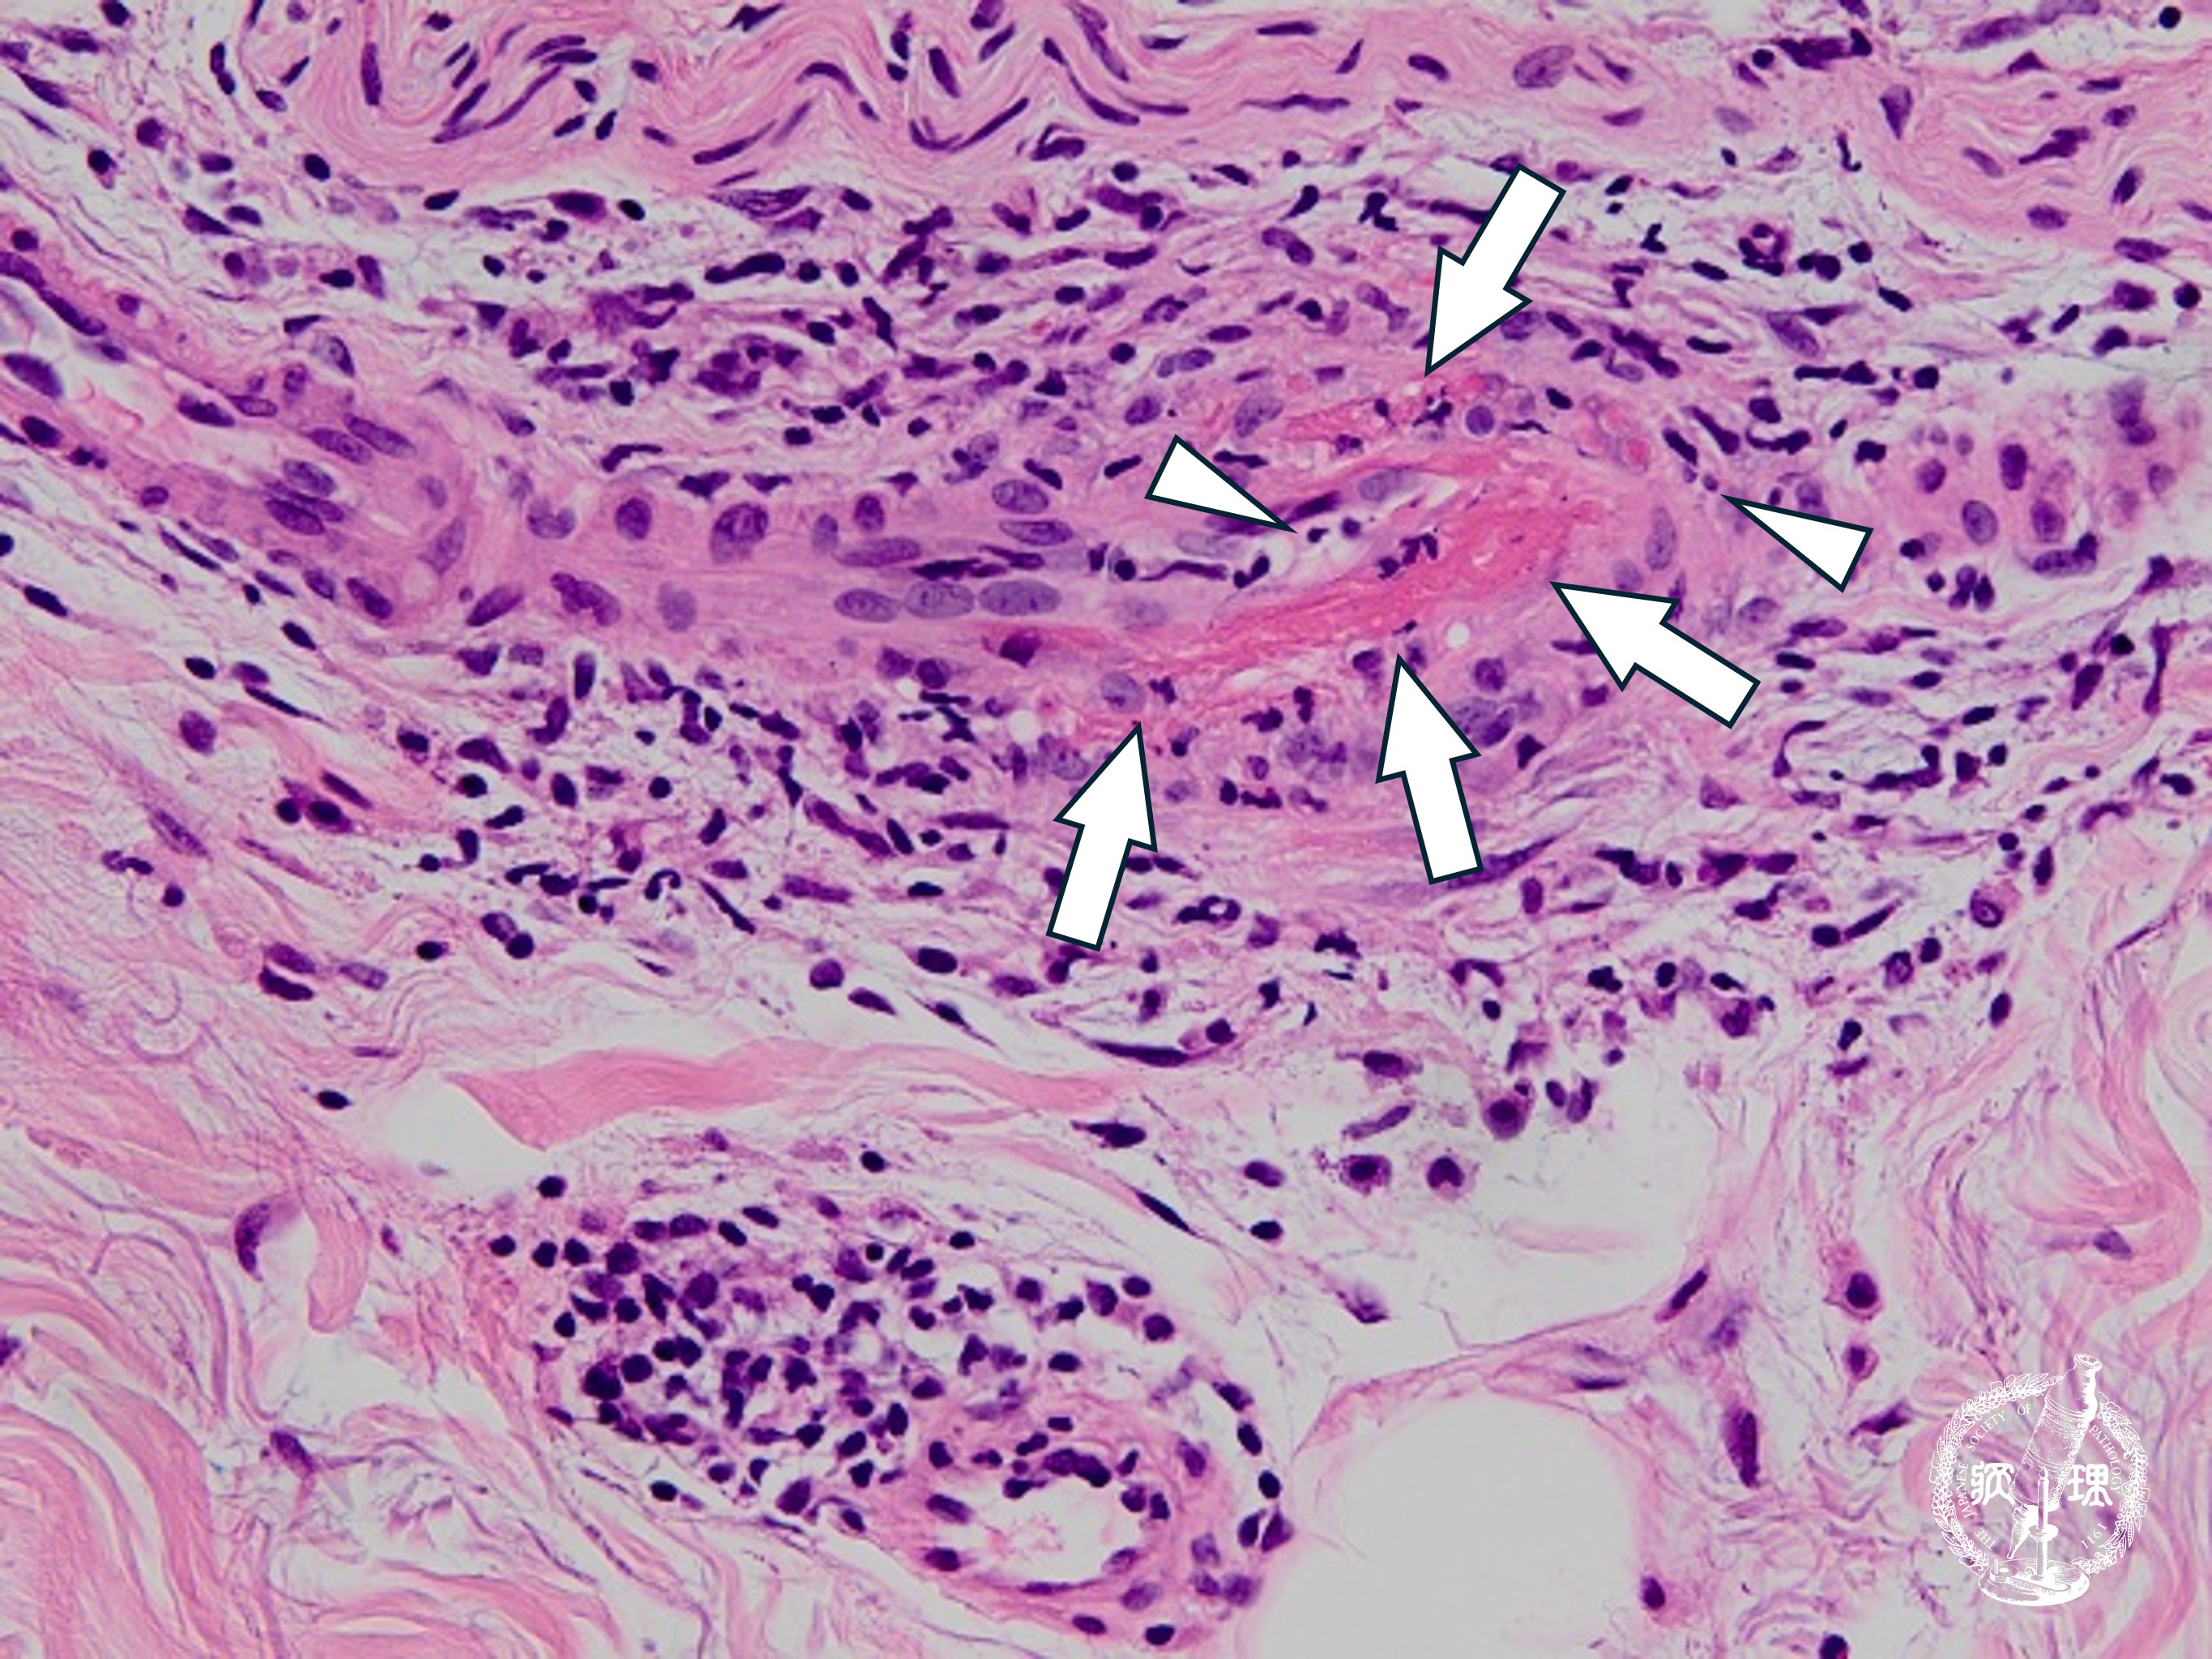

• 母斑細胞母斑(真皮内・境界・複合)ミクロ像(HE強拡大)